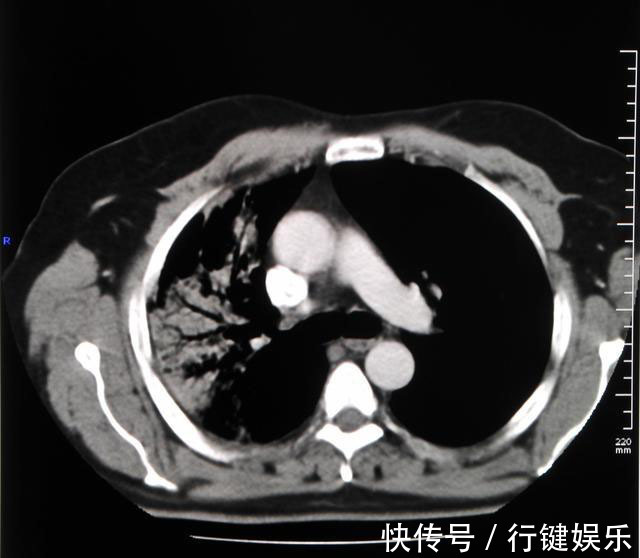

2.小病灶,大转移临床上确实遇到过“小病灶,大转移”的情况,这类肿瘤细胞恶性程度高,增殖快,容易通过血行转移到别处,通常发生在小细胞肺癌、低分化肺腺癌等等,癌细胞易转移到颅内、肝脏、骨头等多个部位,原发病灶虽然很小,早期就有可能出现远处脏器转移,这时候意味着晚期肺癌,失去了手术机会。体检时肺部病灶可能并不明显,但细胞增殖快,易脱落,循血液流入其他脏器定植。